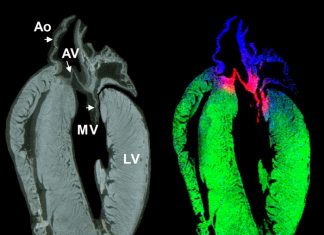

Study: Imaging collagen – a new technique for therapeutics?

Myocardial infarction, or a heart attack, affects over 800,000 people in the U.S. every year. Following a heart attack, a scar forms on the...